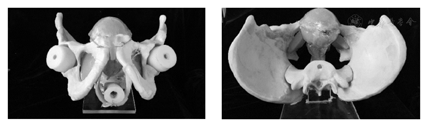

单体器官的材料选择需着重考虑材料的仿生力学性能。通过调整PVA水凝胶的成分配比及制作工艺,得到满足盆腔内不同组织器官力学特性的水凝胶,分别进行盆腔内单体器官的制作。图6为制作完成的前列腺和膀胱单体模型。以人体真实解剖结构为依据,将各单体器官逐一装配在骨盆模型内(图7)。

为模拟真实人体内环境,同时便于进行实验研究,将器官群模型放在有机玻璃箱体中,并在箱体内填充琼脂糖。由于琼脂糖在常温下为透明固体,且其弹性模量很小,因此能达到提供器官群支撑力的作用且不影响穿刺力。箱体前端面留有开口,并在开口处粘附一层硅胶薄膜以模拟人体皮肤,可达到模拟会阴经皮穿刺手术的效果。完整的男性盆腔器官群实体模型如图8所示。